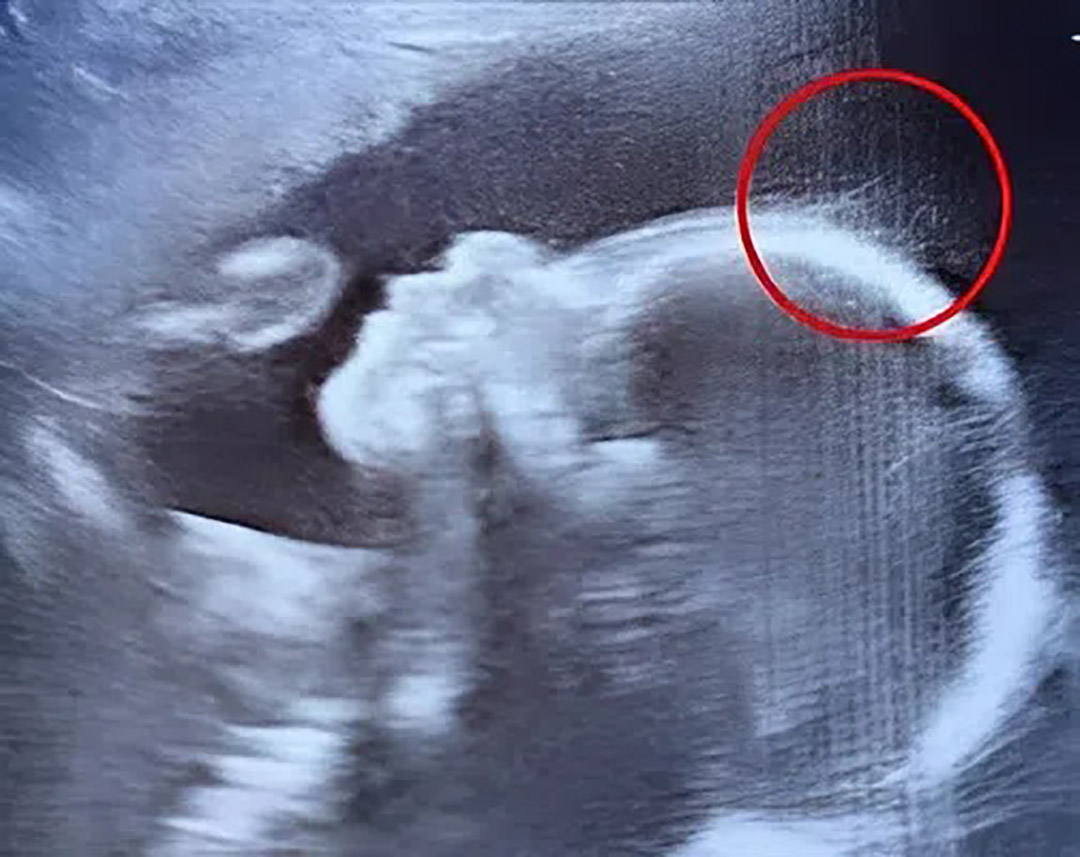

Lors de son échographie de routine à 20 semaines, Emily, jeune maman de 29 ans originaire d'Angleterre, s’attendait simplement à voir le profil attendrissant de son bébé. Mais ce jour-là, une petite phrase lâchée par la technicienne a tout changé : « Ce sont... des cheveux ? » Sur l’écran en noir et blanc, une silhouette se dessinait avec déjà, semble-t-il, une chevelure visible. Une anecdote qui a fait sourire Emily… sans imaginer une seconde ce qui l’attendait.